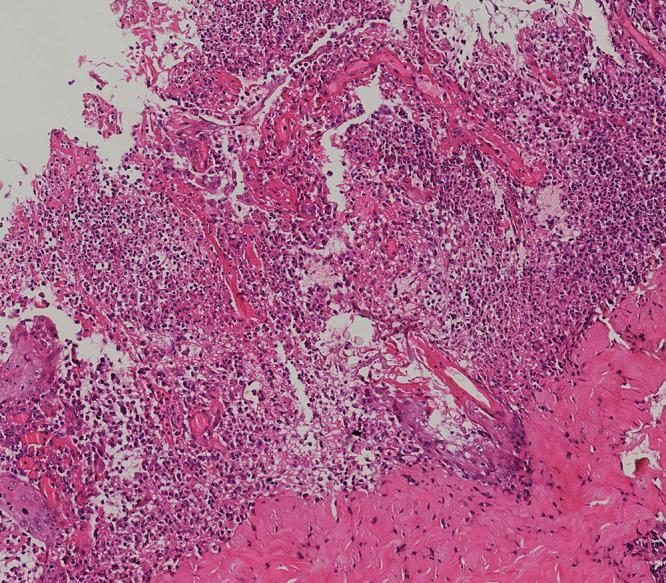

The 11-year-old pediatric patient in the case initially diagnosed with acute febrile neutrophilic dermatosis was eventually confirmed as pustular PG through histopathological examinations of skin and other relevant examinations. The medical condition is lessened after treatment with a combination of glucocorticoids and adalimumab.

该病例中的11岁儿科患者最初被诊断为急性发热性嗜中性皮病,最终通过皮肤组织病理学检查及其他相关检查确诊为脓疱型PG。经糖皮质激素和阿达木单抗联合治疗后病情缓解。